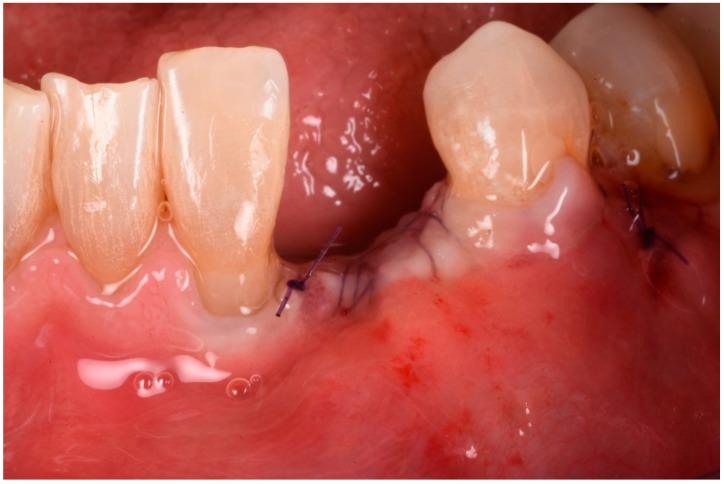

Guided bone regeneration (GBR) has represented a challenge for clinicians in the past 30 years, and the literature has well described many different surgical options such as d-PTFE membranes, titanium grids, or autogenous bone harvested from the posterior mandible. All of the previously mentioned techniques have shown a high rate of complications but, in the last decade, a new membrane made of xenogenic bone was introduced. Most of the publications regarding its application report very few and mild complications. In this article we will suggest a new application using segmented xenogenic bone sheets instead of autogenous bone to correct severe ridge deformity. : Xenogenic bone sheets have been studied extensively over the past decade and have proven effective, with a very low rate of complications when used to reconstruct bone atrophies. The technique presented in this paper aims to reduce morbidity, avoid the need for intra-oral graft harvesting, and minimize both surgical time and post-operative discomfort. : Xenogenic bone sheets of equine origin were used to reconstruct severe 3D bone defects in five patients requiring dental implants. The segmentation of the sheet allowed the operator to rebuild the missing bone walls and achieve optimal anatomy without compromise. Furthermore, using different sizes and thicknesses of the bone sheets allowed safe procedures preventing early exposure of the membranes. CBCT of the defects before and after 8 months of healing were measured with Exocad software to assess the volumetric gain. Histological analysis performed on one site showed integration of the bone lamina and live bone underneath. : In all five cases evaluated the ridge deformities were successfully corrected and all patients' implants have functioned for more than two years to date. The average horizontal bone gain in these five cases was 6.18 mm (±1.19 mm) while the vertical gain was 9.70 mm (±2.39 mm). : This new application of flex cortical sheets simplifies the surgical procedure for both operator and patient, reduces morbidity and post-operative complications, and shows promising signs for resolving complex 3D bone reconstructions.

在过去30年里,引导骨再生(GBR)一直是临床医生面临的一项挑战,文献中已经详细描述了许多不同的手术选择,如双层聚四氟乙烯(d-PTFE)膜、钛网或从下颌后部获取的自体骨。上述所有技术都显示出较高的并发症发生率,但在过去十年中,一种由异种骨制成的新型膜被引入。关于其应用的大多数出版物报告的并发症很少且很轻微。在本文中,我们将提出一种使用分段异种骨片代替自体骨来矫正严重牙槽嵴畸形的新应用。:在过去十年中,异种骨片已被广泛研究,并已被证明是有效的,用于重建骨萎缩时并发症发生率非常低。本文介绍的技术旨在降低发病率,避免口内取骨的需要,并将手术时间和术后不适降至最低。:使用马源异种骨片为五名需要种植牙的患者重建严重的三维骨缺损。骨片的分段使手术者能够重建缺失的骨壁并实现最佳解剖结构而不受影响。此外,使用不同尺寸和厚度的骨片可进行安全操作,防止膜过早暴露。使用Exocad软件测量愈合8个月前后缺损的锥形束计算机断层扫描(CBCT),以评估体积增加情况。对一个部位进行的组织学分析显示骨板与下方活骨的整合。:在评估的所有五例病例中,牙槽嵴畸形均得到成功矫正,所有患者的种植体至今已正常使用两年多。这五例病例的平均水平骨增量为6.18毫米(±1.19毫米),而垂直增量为9.70毫米(±2.39毫米)。:这种柔性皮质骨片的新应用简化了手术者和患者的手术过程,降低了发病率和术后并发症,并显示出解决复杂三维骨重建问题的良好前景。